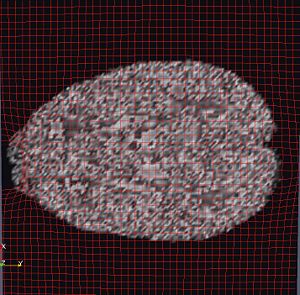

OMT Deformation Grid on DWI

• Preliminary results with DWI baseline image correction.

• DWI and MRI image intensity normalization using CSF and White-Matter/Grey-Matter segmentations performed to make sure both image volumes are on same footing so that Mass Transport mapping is found without introducing structural distortions.